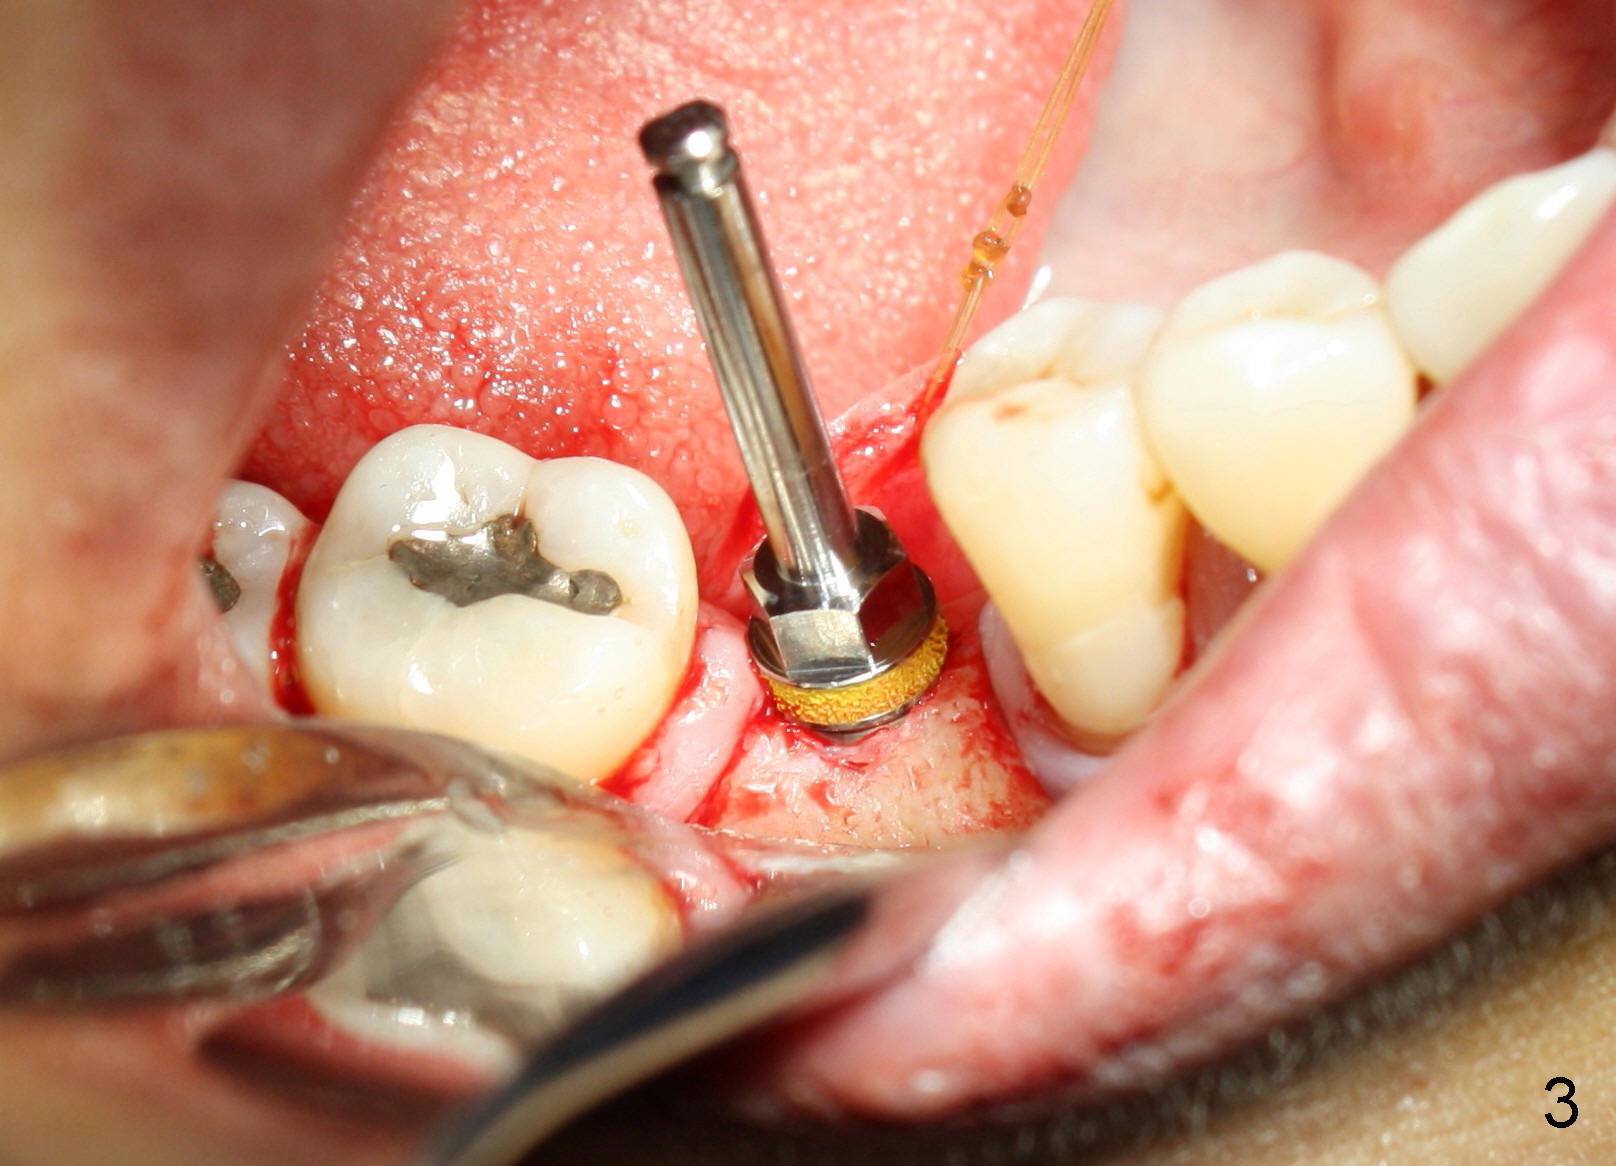

Due to unavailability of bone-level implant, a tissue-level implant is to be placed as a backup (Fig.1: 4.5x17 mm). Osteotomy is initiated with 1.5 mm pilot drill at depth of ~ 10 mm; the trajectory appears to be as good as expected (Fig.2). Osteotomy is gradually increased to 4.5x17 mm, followed by insertion of 4.5x17 mm tap (Fig.3,4). The ostetomy appears to be deviated lingual (Fig.5). When the tap is removed, the buccal plate appears to be thin (Fig.6). A tapered implant is placed (Fig.7).